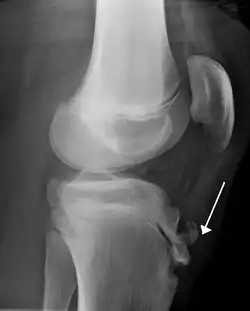

![]() منظر جانبي للركبة بالأشعة السينية، يُظِهر تجزؤ أحدوبة الظنبوب وتورم حاد في الأنسجة الرخوة. منظر جانبي للركبة بالأشعة السينية، يُظِهر تجزؤ أحدوبة الظنبوب وتورم حاد في الأنسجة الرخوة. | |

وتشمل عوامل الخطر الاستخدام الزائد للمفصل، وخاصةً في الرياضات التي تنطوي على الجري أو القفز.[1] تنطوي الآلية على تكرار وزيادة التوتر على الصفيحة المشاشية من أعلى قصبة الساق.[1] التشخيص يعتمد عادةً على الأعراض.[1] و قد تكون الأشعة السينية العادية إما طبيعية أو قد تُظِهر تجزؤ عظمي في المنطقة المرتبطة.[1]